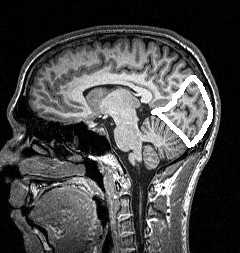

Локализация патологического очага при МРТ головного мозга начинается определения расположения очага по отношению к намёту мозжечка. Поэтому образования выше намёта относятся к супратенториальным, а все что ниже - к инфратенториальным.

МРТ головного мозга. Срединный сагиттальный срез. Намёт мозжечка (стрелка).